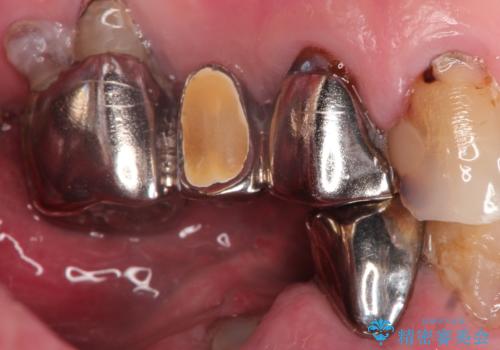

- 奥歯がなくて咬めないのと、全体的に見た目をよくしたいとのことで来院されました。

下顎の両側の奥歯が欠損しており、入れ歯をお持ちでしたが、うまく咬めずにほとんど使用していない状態でした。

上顎は全体的にクラウンの入れ替えと、下顎はインプラントの提案もしましたが、希望されなかったのでノンクラスプデンチャーの製作をする治療計画としました。

奥歯が欠損しており、上下の前歯が強く咬合する可能性があったので、上顎前歯の裏側は金属のものにしました。